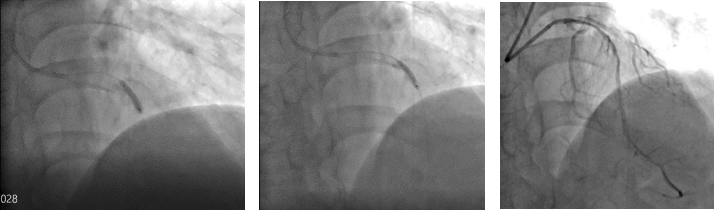

冲击波球

在楚天舒主任指导下,团队顺利使用Shockwave IVL震波球囊对钙化病变处进行多个周期的冲击波治疗。治疗中可见冲击波球囊逐渐扩张开顽固钙化区域,冲击波治疗后复查造影可见左前降支近中段的钙化狭窄处明显改善。术中植入的2枚药物洗脱支架在行IVUS中可见支架贴壁和膨胀良好,血管扩张成形满意。术中患者无明显不适,未见低血压、ST改变及心律失常,术后患者胸痛症状明显好转。目前,该患者病情平稳,胸痛症状完全缓解。